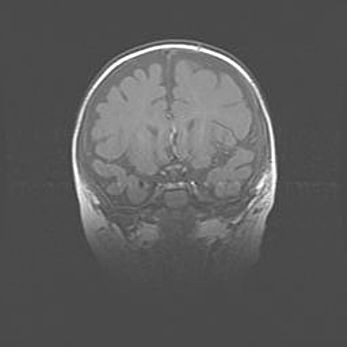

Множественные кисты обоих полушарий головного мозга, наибольшая из них в правой затылочной области. Ассиметричная атрофическая гидроцефалия.

Возраст: 7 месяцев

Вес: 5660 г

Пол: мужской

Окружность головы: 41,5 см

Срок гестации: 28-29 недель

Кисты головного мозга развиваются в результате многоочаговых некрозов вещества мозга и возникают вследствие перенесенной перинатальной инфекции, менингитов, энцефалитов, асфиксии, родовой травмы, расстройств мозгового кровообращения различного генеза. Образованию кист в веществе головного мозга плодов и новорожденных способствуют такие факторы, как высокое содержание в нем воды, недостаточная (или отсутствие) миелинизация и слабая астроглиальная реакция на повреждение.

Кисты могут сочетаться с гидроцефалией и другими поражениями головного мозга.